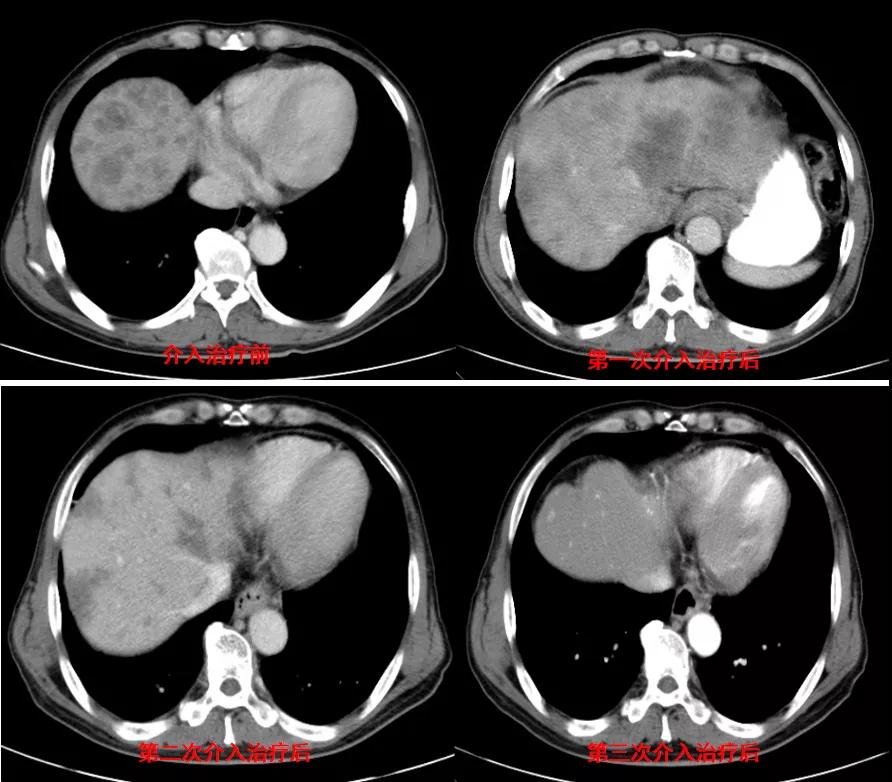

诊治经过:2020年11月25日患者行经皮动脉化疗灌注栓塞术(铂类+氟尿嘧啶);2020年11月30日免疫组化及基因检测结果为:ERBB-2扩增(9倍),VEGFR未突变,MSI微卫星低度不稳定,错配修复蛋白部分缺失(dMMR),MSH2(+弱),MLH1(-),MSH6(+),PMS2(-),CDX2(-),Villin(+),CK8/18(+),Ki67(5%+),CD56(-),Syn(-),CgA(-);患者为HER2阳性,患者肝脏病灶很多,残余正常肝脏体积小,需要寻找对肝功能影响小且抗瘤效果明显的治疗,因此联合吡咯替尼进行系统治疗。2020年12月14日复查结果提示肝脏病灶明显缩小(PR)。结果见图2。

图2